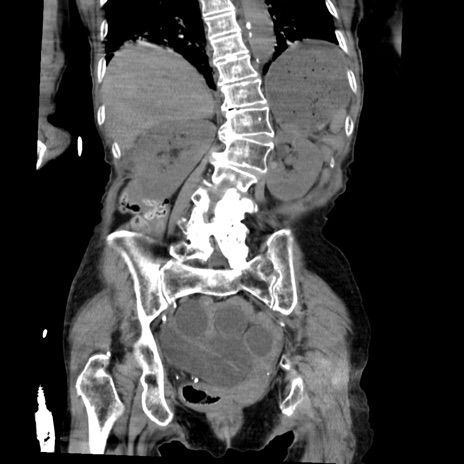

症例27(冠状断像)

【症例】80歳代女性

【主訴】嘔吐、腹痛

【現病歴】数時間前より嘔吐あり。心窩部痛出現し、徐々に右下腹痛あり。その後も数回嘔吐あり救急搬送となる。

【身体所見】腹部は膨隆しているが軟らかく圧痛なし。腸雑音はやや亢進。

【データ】WBC 12000、CRP 19.05